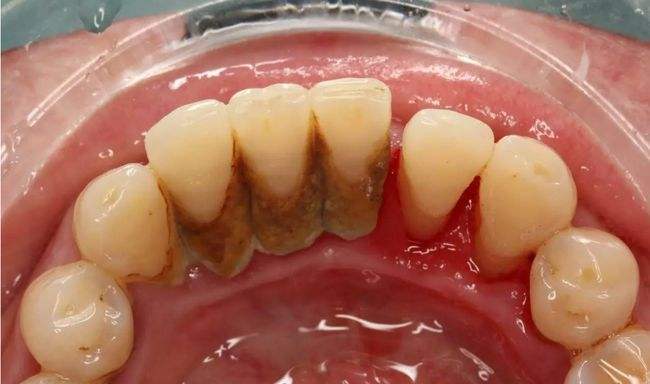

牙龈炎展示图

牙龈炎的症状和治疗方法 牙龈炎是指牙龈组织的炎症,通常由细菌感染

牙龈炎图片及症状图片牙龈炎症状有哪些该怎么办